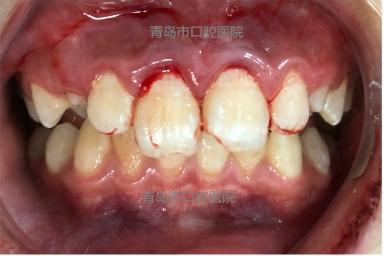

孩子一个不小心磕伤了两颗大门牙,血流不止,拍片一检查,两颗门牙从牙根中1/2处折断,牙齿还能有救吗?3月7日下午5点,一位焦急的家长带着流泪不止的孩子赶到青岛市口腔医院口腔急诊科。

在口腔急诊科诊室,张倩妮医生、刘靖医生仔细检查了患儿的情况。患儿男,11岁,下午3点左右不慎跌倒致上前牙外伤,于外院就诊拍片检查,两颗门牙牙根根中折断。

第一次对接复位尝试,拍片后发现折断牙齿未完全对接复位。此时,刚刚忙完科内病人诊治工作的谭军艳医生,再次来到急诊科协助诊疗。由张倩妮医生与谭军艳医生联合治疗,在赵海平护士配合下,经多次复位,拍片确认,顺利将折断牙完全复位,达到预期治疗效果。

看到跟以前几乎一模一样的牙齿,孩子从最初的惊慌害怕中恢复过来,还跟护士阿姨开起了玩笑,说担心自己还没有完成作业。医生叮嘱,断根接回去后,需小心呵护,两周后复查。